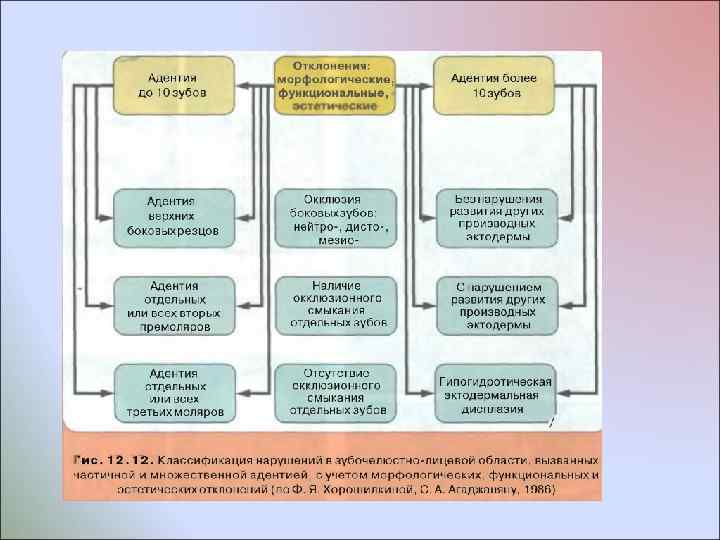

За рубежом отдельные авторы различают сле дующие варианты врожденного отсутствия зубов с учетом их количества: менее 6 зубов, более 6 зубов и полное отсутствие их зачатков. В период прикуса временных зубов отсутствие их зачатков называют гипо , олиго или анолактодентией; В период прикуса постоянных зубов - гипо , олиго или анодентией Такое многообразие терминов неудобно в практической работе и их применение не является точным, так как в периоде прикуса временных зубов важно в первую очередь учитывать, каких временных зубов нет, отсутствуют ли при этом зачатки постоянных зубов, какие именно и сколько; как отразилось отсутствие зубов на формировании зубочелюстной системы и лица; каков будет план комплексных лечебных мероприятий и в какой последовательности они будут применены; каков долгосрочный прогноз лечения. В периоде прикуса постоянных зубов важно учитывать, какие именно зачатки зубов отсутствуют; как расположены имеющиеся зубы и как они смыкаются в окклюзии; сколько сохранилось в зубных рядах временных зубов и каково состояние их корней; сочетается ли врожденное отсутствие отдельных или всех зубов с нарушением развития других производных эктодермы (волос, кожи, ногтей, хрусталика глаза, слизистых оболочек) или нет; каков будет план комплексных лечебных мероприятий и в какой последовательности они будут применены; каков долгосрочный прогноз лечения

За рубежом отдельные авторы различают сле дующие варианты врожденного отсутствия зубов с учетом их количества: менее 6 зубов, более 6 зубов и полное отсутствие их зачатков. В период прикуса временных зубов отсутствие их зачатков называют гипо , олиго или анолактодентией; В период прикуса постоянных зубов - гипо , олиго или анодентией Такое многообразие терминов неудобно в практической работе и их применение не является точным, так как в периоде прикуса временных зубов важно в первую очередь учитывать, каких временных зубов нет, отсутствуют ли при этом зачатки постоянных зубов, какие именно и сколько; как отразилось отсутствие зубов на формировании зубочелюстной системы и лица; каков будет план комплексных лечебных мероприятий и в какой последовательности они будут применены; каков долгосрочный прогноз лечения. В периоде прикуса постоянных зубов важно учитывать, какие именно зачатки зубов отсутствуют; как расположены имеющиеся зубы и как они смыкаются в окклюзии; сколько сохранилось в зубных рядах временных зубов и каково состояние их корней; сочетается ли врожденное отсутствие отдельных или всех зубов с нарушением развития других производных эктодермы (волос, кожи, ногтей, хрусталика глаза, слизистых оболочек) или нет; каков будет план комплексных лечебных мероприятий и в какой последовательности они будут применены; каков долгосрочный прогноз лечения